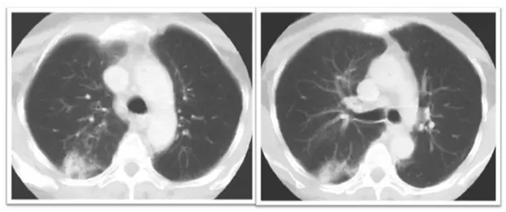

放射性肺炎早期表現(xiàn)

放射性肺炎的CT表現(xiàn)

早期:照射肺野內(nèi)散在的小片狀磨玻璃樣影,密度淡薄,邊緣模糊。

中期:表現(xiàn)為不按肺葉、肺段分布的肺實(shí)變,其內(nèi)可見有支氣管充氣征,肺泡囊、小葉間膈增厚,部分邊緣整齊,部分邊緣呈星狀,可超出放射野。

晚期:表現(xiàn)為肺野內(nèi)長(zhǎng)條狀、大片狀密度增髙影,邊緣銳利呈“刀切狀”,同側(cè)胸膜增厚,支氣管、肺門、縱膈、橫縱膈牽拉移位等肺容積縮小改變。